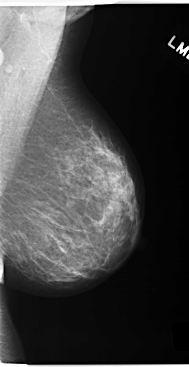

C_0168_1.LEFT_MLO

LEFT_MLO LINES 5872 PIXELS_PER_LINE 3016 BITS_PER_PIXEL 12 RESOLUTION 50 NON_OVERLAY